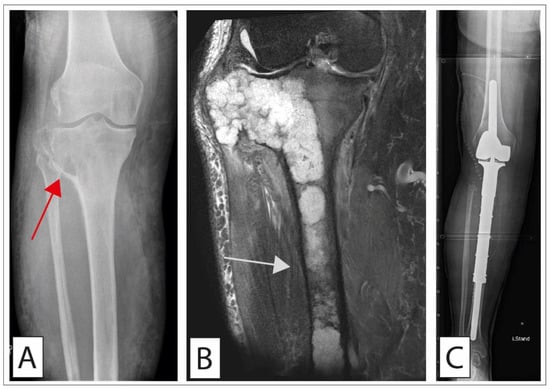

2.2.1. Surgical Therapy

2.2.2. Limb-Sparing Surgery (LSS) Versus Amputation